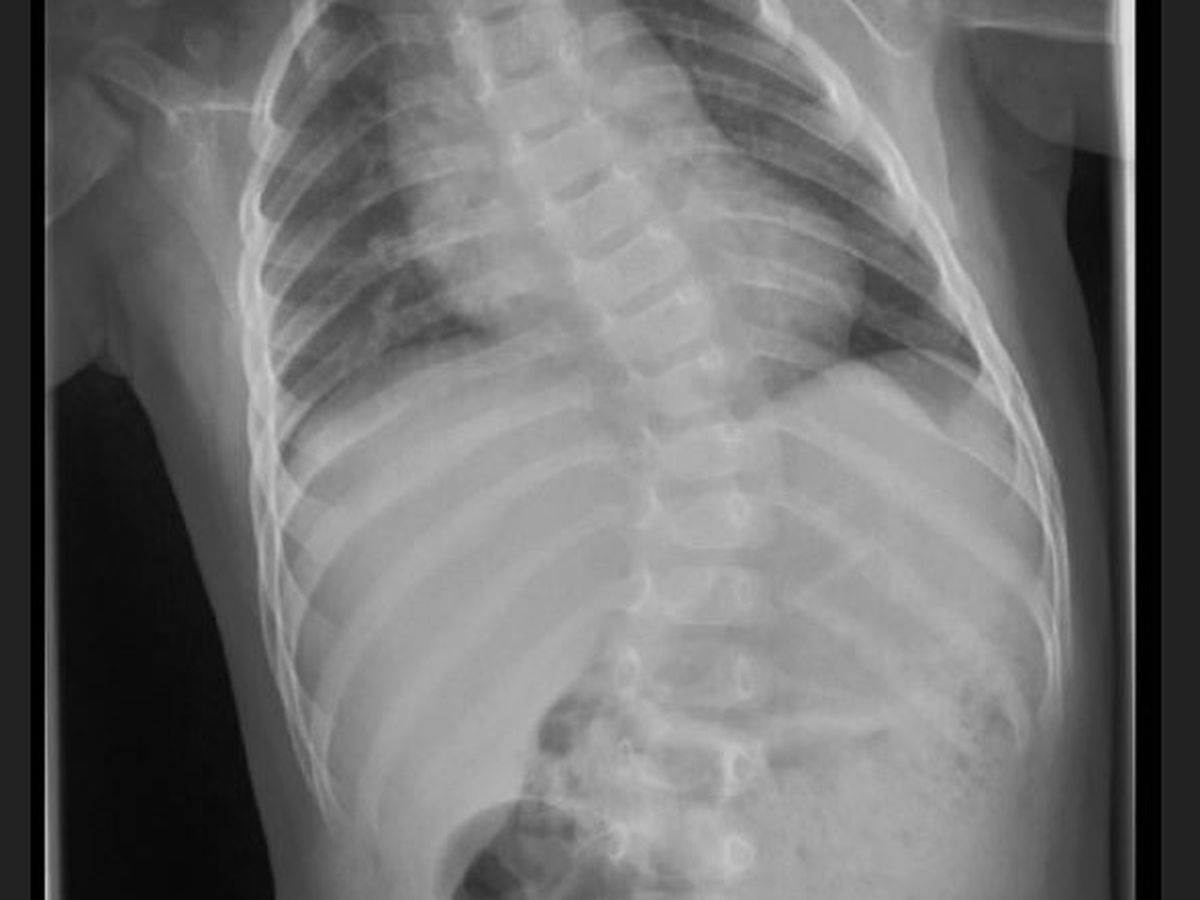

About two weeks ago my wife and I got the saddest news you could ever imagine receiving as young parents. We were informed that Liam, our happy and loving baby boy, has progressive idiopathic infantile scoliosis. Our Dr. advised us that this is very serious and untreated it would become fatal and that Liam needed immediate intervention. We weren’t prepared for this news.

Liam was born with scoliosis. We noticed the scoliosis at birth and unfortunately followed the advice from our Dr. at the time to keep a close eye on him and see if it would go away.

At about 10 months of age, Liam’s scoliosis was getting so severe we could see it through his clothing and in his back motor skills. His spine was not only curved but was also rotated causing his back to protrude on the left side of his body. Our pediatrician finally suggested we seek out specialists to work with.

Liam's spine is curving towards his heart. This only happens in about 10% of scoliosis cases and Dr.’s are advising us that this will impact his cardiovascular and pulmonary system, so we are left with no choice.